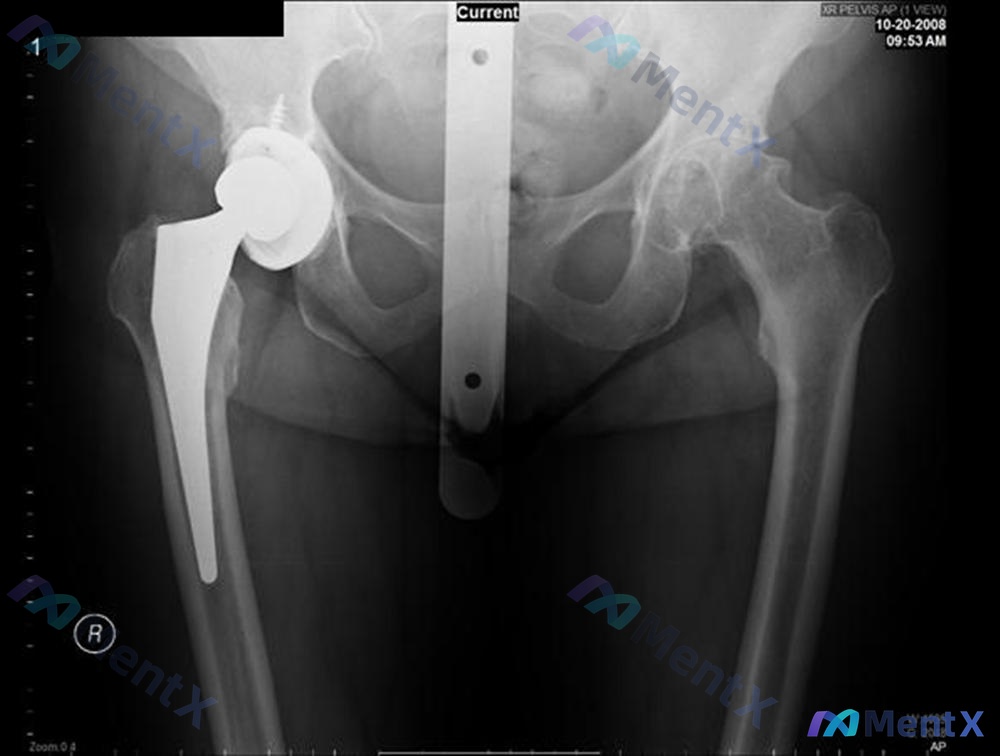

提供了一张骨盆正位X光片(图A)。

- 右侧人工髋关节置换术后改变,报告写的是“假体位置及固定尚可”,骨-假体界面没看到明显透亮线或骨溶解,也没移位断裂。

- 左侧(没手术侧)倒是有比较严重的表现:股骨头外形欠圆、关节间隙明显变窄、有明显骨质增生(骨赘)、软骨下骨硬化,Shenton线不太连续——报告提示是严重的退行性骨关节炎。